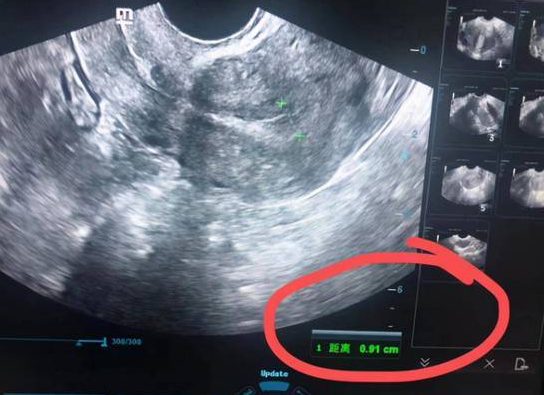

试管移植胚胎落地生根需要一个良好的着床环境,而内膜厚度就是影响着床的重要因素之一。一般来说,内膜厚度在8-12mm之间时,着床率最高,因此在试管移植前要保证内膜厚度达到这个范围。如果内膜过薄或过厚,都会对胚胎的着床造成不利影响。

在做试管移植前医生都会对女性的子宫内环境和子宫内膜厚度等进行检查的,只有当女性的子宫内膜厚度达到一定条件才可进行移植,而子宫内膜回声不均匀,则说明内膜厚度存在异常,并不会适合移植。若是子宫内膜存在下面这些问题都会影响到胚胎着床。